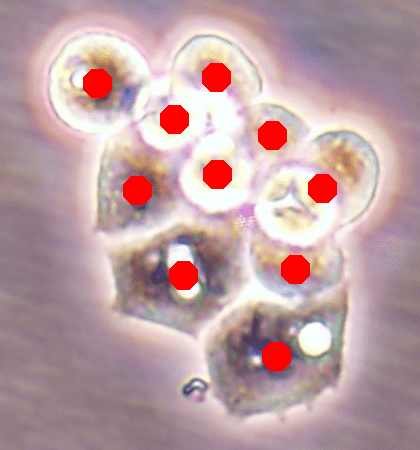

Before the advances in deep learning, the traditional approach for cell detection/segmentation is to employ low-level handcrafted features, reflecting color, edge, and shape characteristics of cells. This approach has given promising results when the features are defined properly, as a good representation of the visual cell characteristics. On the other hand, these characteristics may change from one cell type to another (see Fig. 1) and new features need to be defined to meet the cell characteristics of a new type. Additionally, when there exists heterogeneity in the visual characteristics of the same cell type, using a single model may not be sufficient to detect all cells of this type, particularly for cancer cells which are exploited more in high throughput screening.

![]() |

| (a) | (b) | (c) |

We test our DeepDistance model on three datasets, each of which consists of live cell images of a different cell line. They are the CAMA-1, MDA-MB-453, and MDA-MB-468 human breast cancer cell lines. The images in all datasets were acquired at magnification and pixel resolution. An example image from each dataset is shown in Fig. 1. As seen in this figure, cells might be visually different within and across different cell lines.